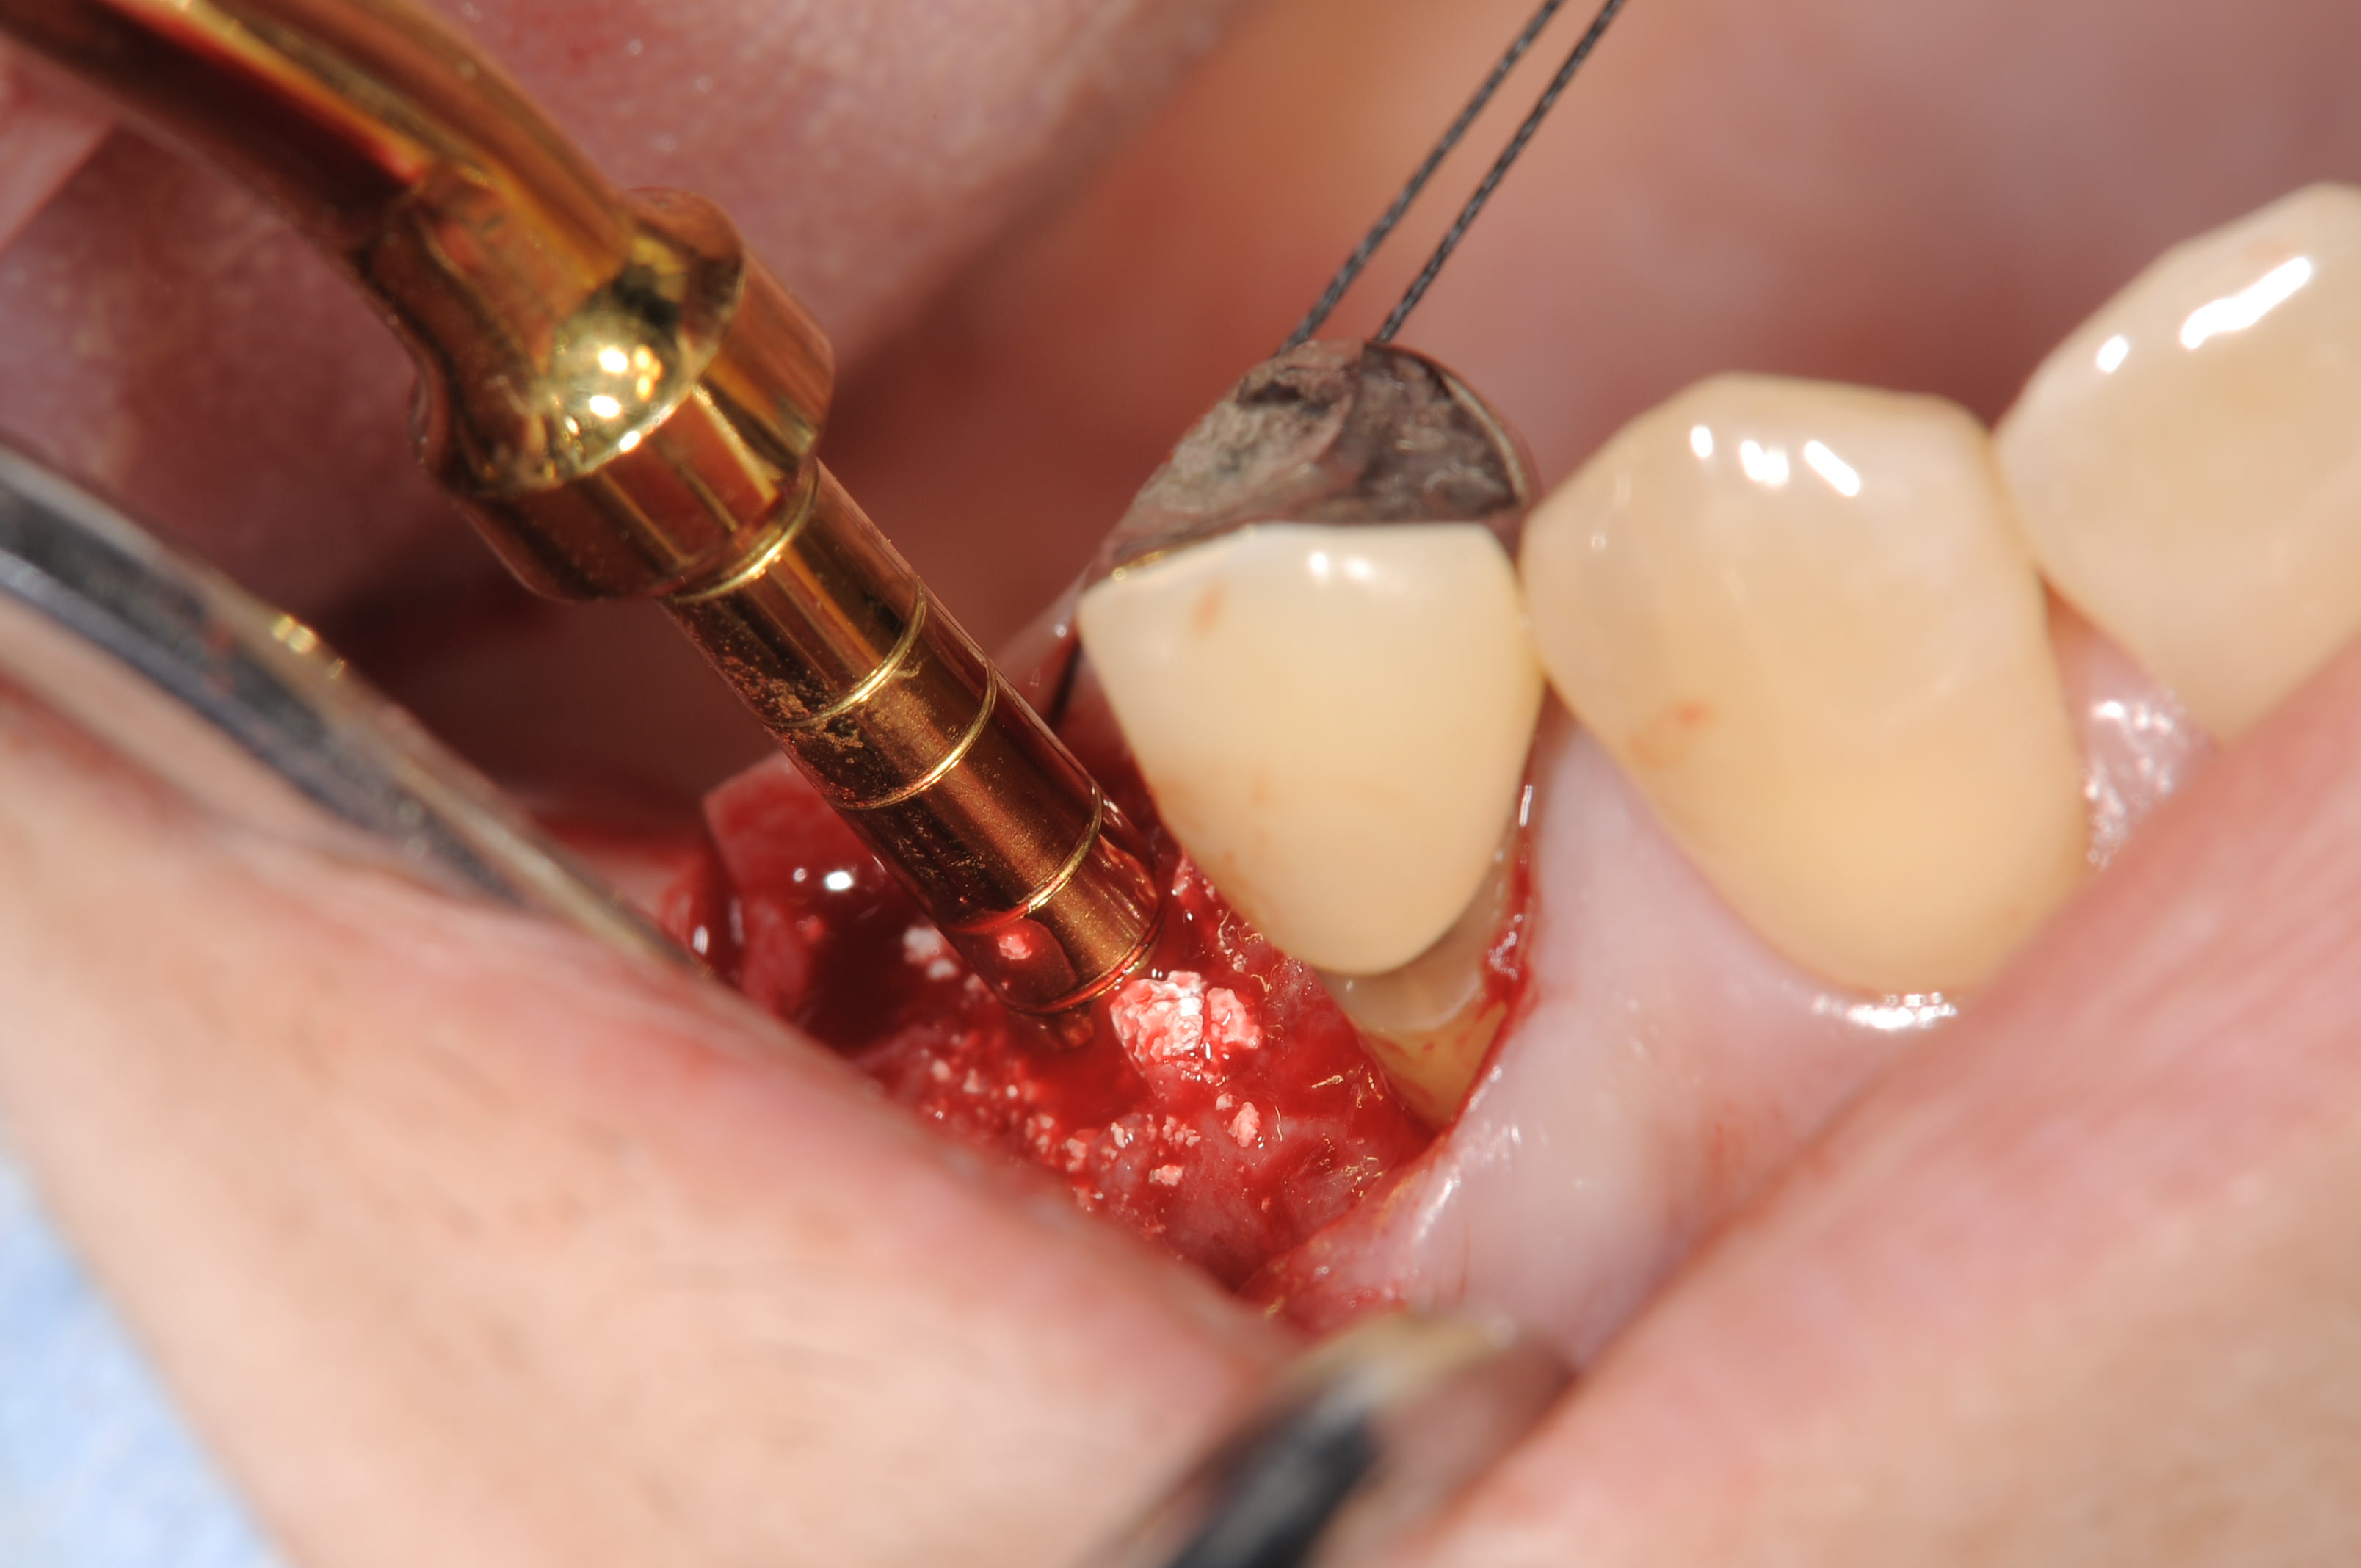

既存骨の厚みが6mmでしたので、ストローマンティッシュレベルインプラントのWN10mmをサマーズテクニックで埋入しました。

ストローマンWNの場合、、皮質骨の部分にコロナルフレアーで固定が取れやすいので、ソケットリフトの場合は特に使いやすいと思います。

オステオトームテクニックで骨補てん材にオスフェリオンを使用しています。

ストローマンティッシュレベルインプラントの埋入中です。